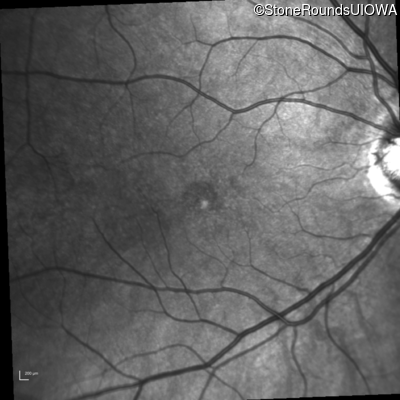

Fluorescein Angiography - Left - 20/40

Exemplar